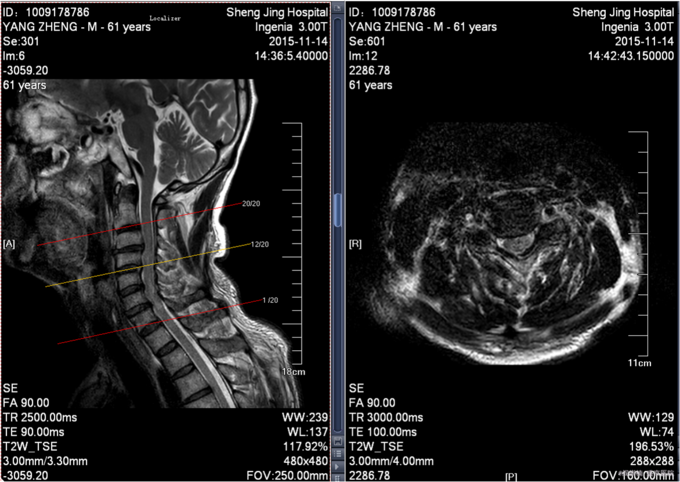

患者于2015年11月13日15:30左右因在工厂2米高管道上作业不慎坠落致颈部疼痛,四肢活动受限,受伤后被家人送入当地北台镇医院,输一袋葡萄糖液,转入本溪二院,行口腔科、眼科缝合行X线检查,头颅ct检查。患者及家属为求系统治疗,急来我院,急诊予以行辅助检查,提示:颈4-6棘突骨折,颅骨多发骨折;急诊以“颈椎外伤”为主诊断收入我科。病来患者一般状态无头晕及头痛,,无恶心及呕吐 ,留置导尿中。

前额部敷料包扎中,打开敷料见右眉处7cm大小创口已缝合,无渗出,前额处可见一5cm大小创口已缝合,颈领保护中,触痛。双手感觉减退。患者平乳头以下触觉存在,痛觉及运动消失。屈肘肌力(R4,L4),伸肘肌力(R0,L0),手掌掌屈肌力(R0,L0),手掌背伸肌力(R0,L0)。双手握力(R0,L0)。髂腰肌肌力(L0级,R0级),伸膝力(L0级,R0级),足背伸力(L0级,R0级),足跖屈肌力(L0级,R0级),神经反射:BCR:L(-)R(-),TCR:L(-)R(-),肱桡肌反射:(-)R(-),PSR: L(-)R(-),ASR: L(-)R(-),Hoffmann Sign:L(-)R(-), Babinski Sign L(-)R(-) 双侧桡动脉、足背动脉可扪及搏动,末梢血运良好。

患者入院后完善相关检查,明确诊断,手术指征明确,于2015-11-17日于全麻下行颈椎后路单开门椎板减压,侧块螺钉内固定术,术后经抗炎、止疼等对症治疗后,患者恢复顺利,切口愈合良好,今日可出院。